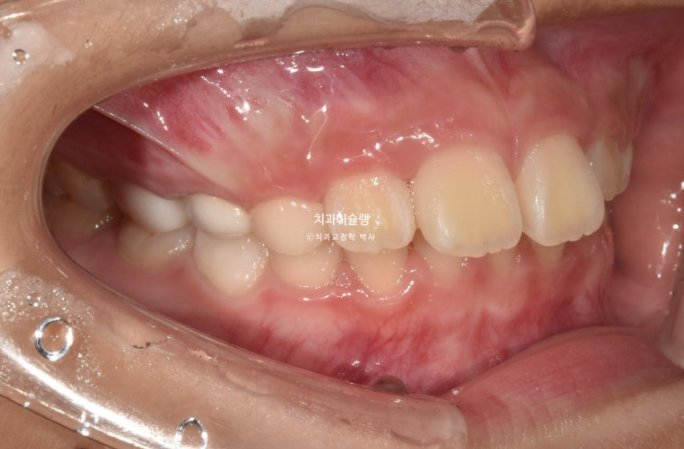

23.10

엑스레이 골격 분석 결과 아래턱이 작은 골격성 2급 부정교합 (소위 무턱)으로 진단되어 무턱치료도 하기로 합니다.

인비절라인 퍼스트의 Mandible advance 기능으로 못 자란 아래턱을 자라게 해줄 수 있습니다.